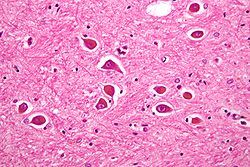

Hepatik ensefalopatiya — kəskin və xronik qaraciyər xəstəliklərinin beyin funksiyalarında törətdiyi geriyədönən və ləngimə xarakterli neyro-psixoloji (şüur, intellektual və hərəkətə nəzarət) dəyişiklərdir. İlk növbədə beyin qabığına məxsus şüur (xarici təsirə cavab və ayıqlıq), intellektual (yaddaş, qavrama, danışma, diqqət, xarakter və s.) və hərəkətə nəzarət funksiyaları pozulur. Proses irəlilədikcə qabığaltı mərkəzlərin fəaliyyəti, hətta tənəffüs mərkəzi də dayana bilir.